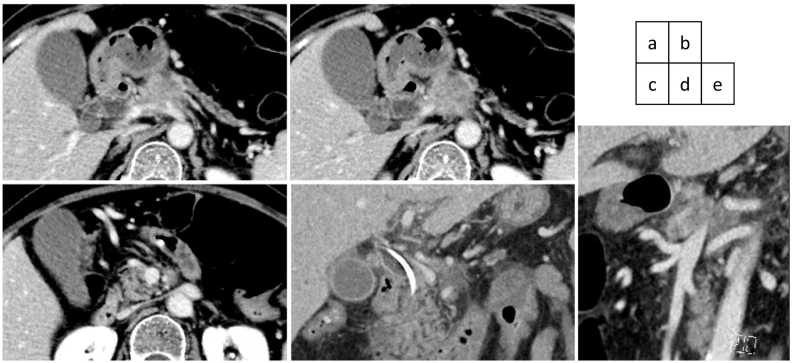

An abdominal computed tomography (CT) scan with dynamic enhancement revealed a 3-cm, ill-defined tumor in the pancreatic body circumferentially invading the CA and SMA (Fig. 1a,c,d,e). The portal vein (PV) was narrowed, and the splenic vein was obliterated by the invading tumor (Fig. 1b,d,e). Nine days after the initial check-up, the serum bilirubin level was 9.5 mg/dL, and endoscopic biliary decompression was done. The CBD was obstructed near the upper border of the pancreatic head (Fig. 2a). A 7 Fr-thick, 7 cm-long plastic internal stent tube was placed. A gadoxetic acid-enhanced magnetic resonance imaging did not reveal any liver metastases. The patient was diagnosed to have a T4N0M0 clinical stage III pancreatic tumor.